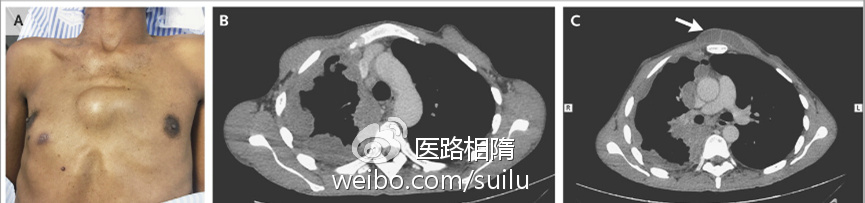

自溃性脓胸

自溃性脓胸是结核性脓胸常见的并发症。结核性脓胸的壁层胸膜破裂,自发排出其内容物,可进入许多组织,最常见的额是胸壁皮下组织。

自溃性脓胸.jpg